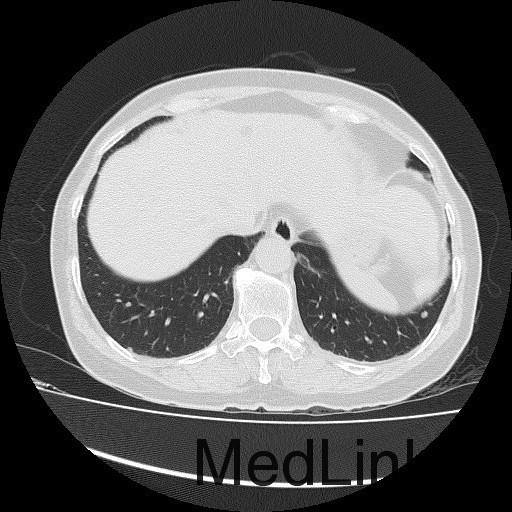

诊断:甲状腺恶性肿瘤(术后);手术后甲状腺功能减退。 治疗:入院时甲状腺球蛋白>455pmol/L,甲状腺素2.793uIU/ml,根据病情于2014-6-3予大剂量碘-131 100mCi清甲治疗;2014年6月全身碘扫示:全身多发异常摄碘组织,考虑甲状腺癌术后双侧甲状腺组织及锥状叶残留并全身多发骨转移。2014年9月胸部CT示:1、双肺多发转移瘤,并胸骨转移;胸1、8、10、腰1椎体内多发结节灶,考虑转移瘤可能性大。2、右肺中叶内侧段、双肺下叶散在慢性炎症。2014年12月全身碘扫:1.全身多处异常摄碘组织,考虑多发骨转移瘤。又于2014年12月复查甲状腺球蛋白抗体90.400U/mL,促甲状腺素6.914uIU/ml。遂于2014-12-22口服250mCi大剂量放射性碘-131。治疗后全身碘扫复查结果提示:2.左肺下叶摄碘组织,不排除转移瘤,建议进一步检查。与2014.6.6检查相比,颈部甲状腺部位放射性浓集灶消失,余病灶放射性浓集程度较前稍降低。

患者又于2015年10月胸部CT复查,结果提示:1、甲癌术后改变;双肺多发转移瘤,大部分病灶较前缩小,左肺下叶病灶较前增多,部分较前增大;胸骨转移;胸1、8、10、腰1椎体内多发结节灶,基本同前,考虑转移瘤可能性大。2、右肺中叶内侧段、左肺上叶舌段及双肺下叶散在慢性炎症。